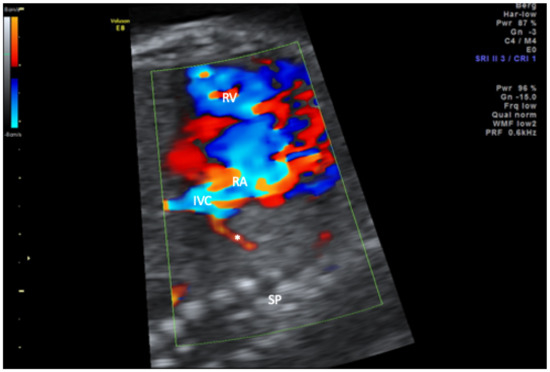

- Michailidis, G.D.; Simpson, J.M.; Tulloh, R.M.; Economides, D.L. Retrospective Prenatal Diagnosis of Scimitar Syndrome Aided by Three-Dimensional Power Doppler Imaging. Ultrasound Obstet. Gynecol. Off. J. Int. Soc. Ultrasound Obstet. Gynecol. 2001, 17, 449–452. [Google Scholar] [CrossRef]